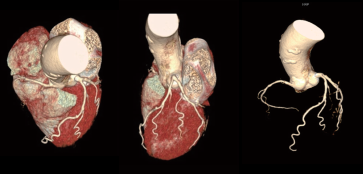

VRT图可见冠脉主干及主要分支血管的走行及心腔的关系。